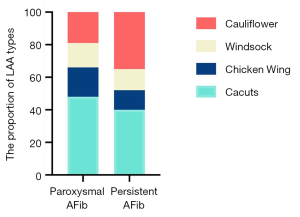

LAA lobes and morphology typing in AFib patients

We also used RT-3D TEE as a tool to determine the number of LAA lobes, and to identify the relationship between the number of lobes and the AFib types. We found that the majority of LAAs had between two and three lobes, while one lobe accounted for a relatively small proportion in our cohort study (Table 3). Also, we identified a trend of long-standing AFib patients having more LAA lobes compared to paroxysmal group patients, however no statistical difference was found (P=0.19). In the paroxysmal AFib group, the LAA morphology typing were ordered as follows: cactus type (46%), cauliflower type (19%), chicken wing type (20%), and windsock type (15%), compared to cactus type (40%), cauliflower type (32%), chicken wing type (16%), and windsock type (12%) in the long-standing group (Table 3, Figure 4). The percentage of cauliflower type LAAs in the long-standing AFib group increased significantly (P<0.001), whereas the proportion of non-cauliflower type LAAs decreased slightly, compared with the paroxysmal AFib group (P≥0.05).